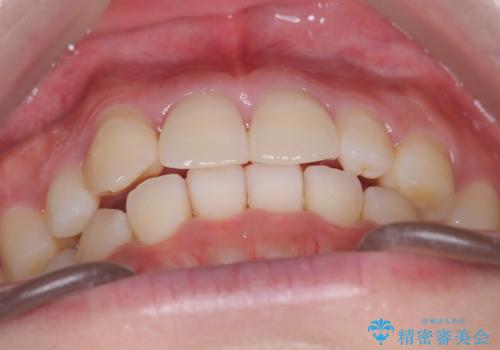

【インビザライン】八重歯が気になる

- 乳歯を抜歯してスペースを確保し八重歯の改善を行いました。

インビザラインをしっかり使用していただいたので、きれいな歯並びになりました。